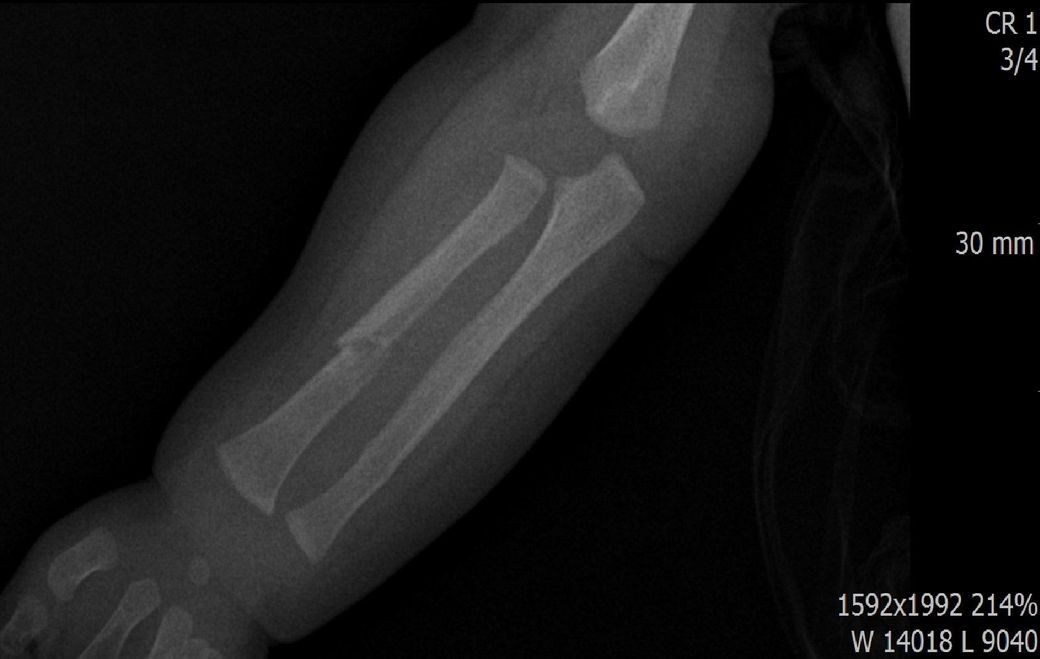

다름이 아니라, 첨부드린 엑스레이(X-ray) 사진처럼 골절 사실을 알게 되고 골절 발생 시점 대략적으로나마 추정시기를 파악하려고 문의 드리게 되었습니다

1) 3월 30일 촬영한 X-ray만으로 정확한 골절 시기를 100% 특정하는 데에는 한계가 있다는 점 충분히 인지하고 있기에 촬영날짜 기준으로 대략적으로 어느정도 시점에서 발생되었을 것으로 추측(ex 당일, 7~10일전, 7~14일 전, 10일 ~ 20일전, 14일 ~ 30일전 등등등)되는지 이해하고 싶습니다.

• 3번 째 사진

골절의 상태를 보고 골절선이 선명하고 부위에 가골이 형성되지않았다면 보통 일주일 이내로 봅니다.

골절선이 보이지만 주변 부위에 가골이 조금씩 있다면 2주 이내.

골절선이 잘안보이고 가골이 보인다면 한달 이내로 판단 할 수 있습니다.